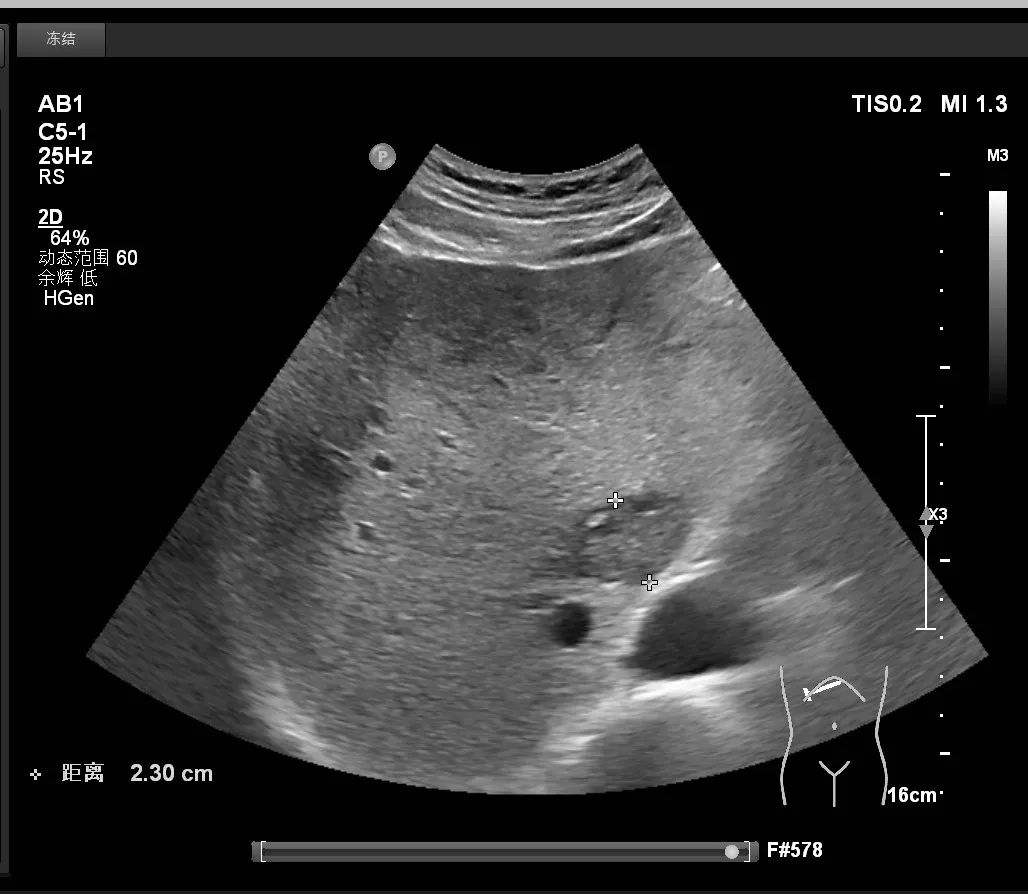

时间可以追溯到2025年1月,超声科一如既往的忙碌着。宋先生按照预约日期走进姚医生的工作室。在就医过程中,姚医生一边检查一边耐心地询问病史。“最近有什么弱点吗?你得了肝炎吗?“在确定患者有肝炎史后,姚医生调整了探头的视角,在患者肝脏区域来回检查。肝左叶一个2厘米的低回声结节引起了她的警惕。根据病史和图像情况,她认为这个结节是恶性的,此刻她的心情有点沉重...

得知测试结果后,宋先生不知所措。看着眼前悲伤的宋先生,姚医生用柔和的声音向他解释了病情,并鼓励他有信心。“你现在最重要的是去上级医院进一步检查,然后积极配合治疗,一定要有信心。”在姚医生的鼓励和建议下,宋先生去上级医院治疗并做了手术。术后病理学证明是肝细胞癌。